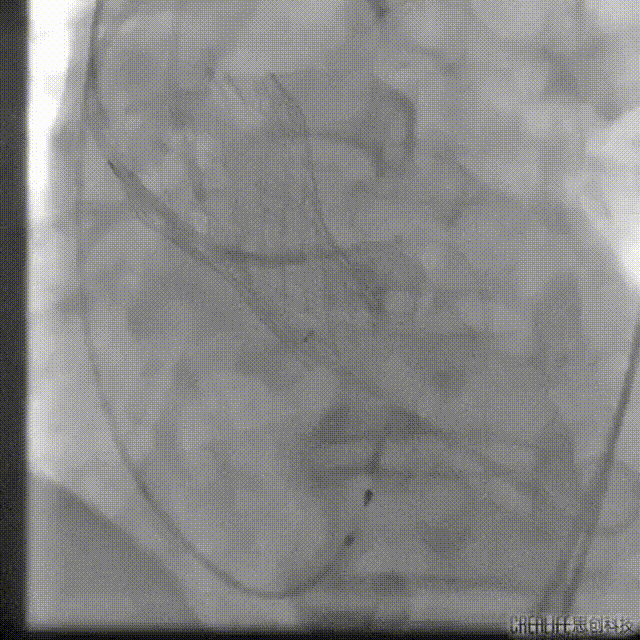

VenusA-Plus 26#瓣膜释放至80%造影

瓣膜释放后造影